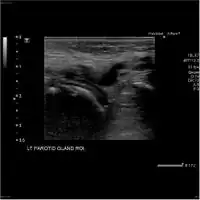

Acute left parotid sialadenitis